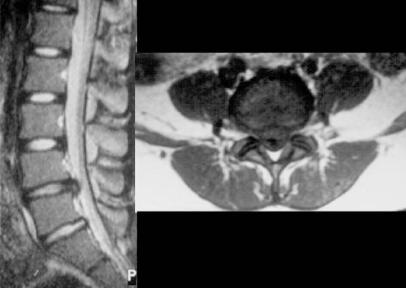

To assess the radiological, clinical features and surgical outcomes of six patients of elementary school age with lumbar disc herniation (LDH).

The surgical findings revealed a protruding disc in five cases and a ruptured disc in one. In addition, separation of the vertebral ring apophysis was observed in 3 cases. The symptoms had disappeared completely at the last follow-up. At the last follow-up, the Japanese Orthopaedic Association score was 10 points in 5 cases and 9 points in 1, and the Kirkaldy-Willis criteria was excellent in all patients. No intervertebral disc space narrowing was observed in any patient at last follow up. In addition, there were no degenerative changes in the vertebral endplate and facet joint.

评估6例小学年龄腰椎间盘突出症(LDH)患者的影像学、临床特征及手术疗效。

手术发现5例为椎间盘突出,1例为椎间盘破裂。此外,3例观察到椎环骨骺分离。末次随访时症状已完全消失。末次随访时,日本骨科协会评分为5例10分,1例9分,所有患者的Kirkaldy-Willis标准均为优。末次随访时所有患者均未观察到椎间盘间隙变窄。此外,椎体终板和小关节无退变改变。